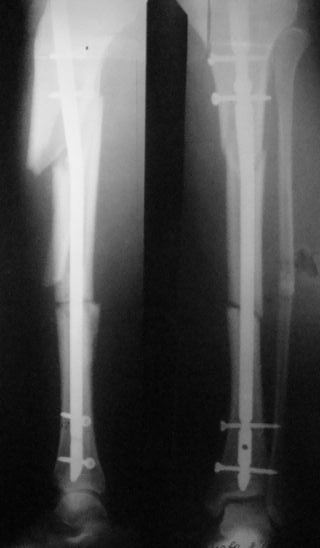

Был тройной перелом голени. Операция была сделана крайне неудачно. Край кости выпирает. Хирург ,проводивший операцию предлагает просто его отпилить. На консультации в другой клинике предлагают извлечь штифт и поставить аппарат Елизарова. Страшно.Подскажите пожалуйста возможно ли исправить ситуацию заменив штифт и правильно соединив обломки. Снимки прилагаю.

Возможно я плохо изложила свою проблему.У меня был перелом обеих костей голени со смещением. 13 января был установлен штифт.Операция была не совсем удачная т.к.сильно выступает острый обломок б.берцовой кости. Очень некрасиво и есть опасность разрыва кожи.

Три ортопеда к которым я обращалась за консультацией считают, что такой результат неприемлем. необходимо извлечь штифт и установить аппарат Илизарова.

Посмотрите снимок.Можно ли оставить всё в таком виде и впоследствии подкорректировать?